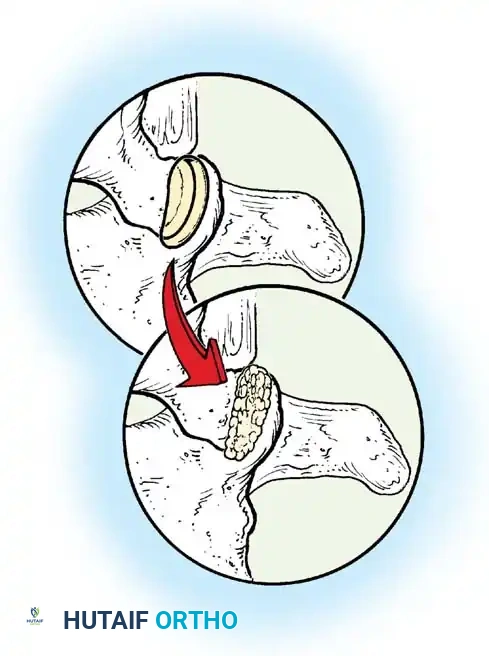

The Hall Technique

The Hall technique offers an alternative method for facet obliteration and grafting, particularly useful in rigid deformities.

Fig. 38-28: The Hall technique of facet fusion, involving sharp excision of the inferior facet and trough creation.

- Sharply amputate the inferior articular facet with a gouge and remove the bone fragment entirely. This exposes the cartilage of the superior facet.

- Remove the exposed cartilage completely with a sharp curet.

- Create a bleeding trough by removing the outer cortex of the superior facet.

- Impact cancellous bone grafts directly into this vascularized trough.

- Complete the procedure with global decortication of the posterior elements.